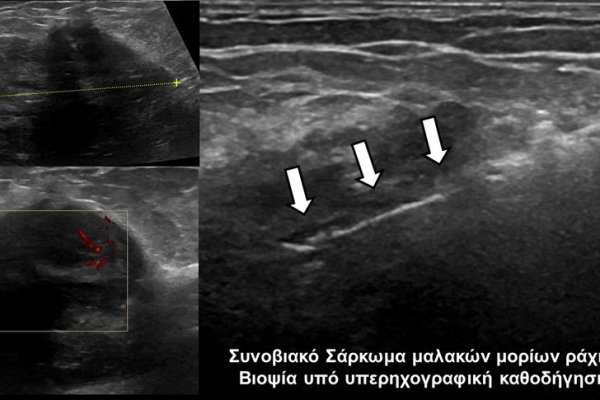

Η οστική βιοψία και η βιοψία όγκων μαλακών μορίων χρησιμοποιείται για την ιστολογική διάγνωση αλλοιώσεων (καλοήθων - κακοήθων / πρωτοπαθών ή μεταστατικών) ή για τη λήψη υλικού προς καλλιέργεια ώστε να αναδειχθεί το μικρόβιο που προκαλεί τη λοίμωξη του μυοσκελετικού συστηματος (πχ σπονδυλοδισκίτιδα). Η βιοψία υπό συνεχή απεικονιστική καθοδήγηση συμβάλλει στην υψηλή ακρίβεια τοποθέτησης της βελόνης εντός της βλάβης με ασφαλή προσπέλαση. Η χρήση σύγχρονων ομοαξονικών συστημάτων βιοψίας (coaxialtechnique) επιτρέπει την λήψη πολλαπλών δειγμάτων με μια μόνο παρακέντηση.